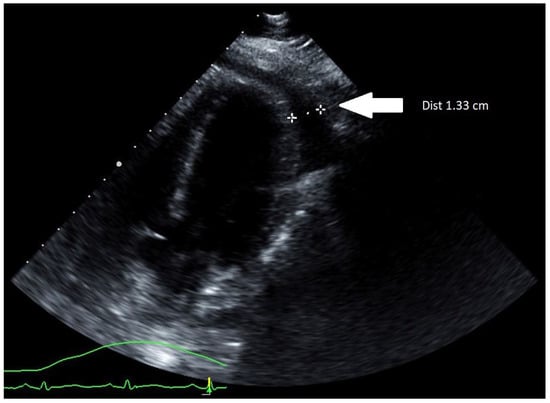

Initial computerized tomography (CT) scan of the chest along with a transthoracic echocardiogram (TTE) showed a small pericardial effusion with normal ventricular size and function. The patient was started on systemic steroid therapy with methylprednisolone 40 milligrams IV every 6 h, colchicine 0.6 milligrams two times daily, along with Oseltamivir 75 milligrams two times daily for influenza A pericarditis. Over the following 12 h, the patient received 4 L of IV crystalloid saline without improvement in her heart rate. Subsequently, she developed hypotension with the median arterial pressure (MAP) falling below 55 mm of mercury leading to left radial arterial line placement. Upon connection of the arterial line to the pressure transducer, the arterial waveform demonstrated pulsus alternans and, at times, pulsus paradoxus. At this point, an urgent TTE was performed and demonstrated an increasing pericardial effusion now measuring 1.33 cm with dynamic images showing cardiac tamponade (Figure 1).

Figure 1. TTE (parasternal long-axis view) showing an increasing pericardial effusion measuring 1.33 cm (marked by two white stars).